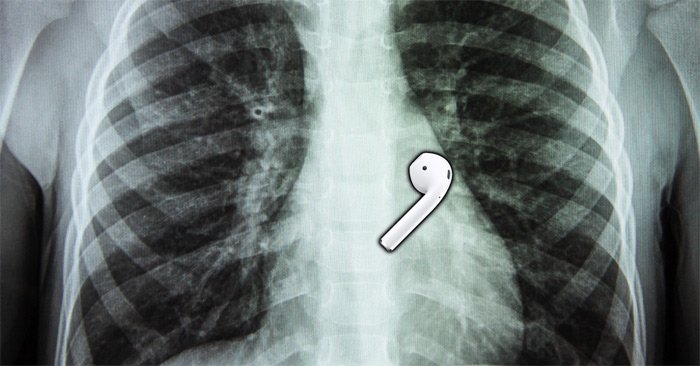

Old  Default Chiếc AirPod vẫn hoạt động tốt sau khi được lấy ra khỏi thực quản người

Đúng như vậy. H́nh ảnh chụp X-quang cho thấy chiếc AirPod đă ở trong thực quản của anh. Rất may, AirPod đă không làm tắc đường ống thở hoặc ở trong dạy dày (pin lithium-ion không tốt cho sức khỏe). Sau đó, anh được các bác sĩ tiến hành lấy chiếc AirPod ra khỏi cơ thể.

Sau khi về nhà, Gauthier nhận thấy chiếc AirPod vẫn hoạt động tốt, dù micro hoạt động kém hiệu quả một chút so với trước.

Đây không phải là lần đầu tiêng AirPod sống sót sau khi “chui” vào cơ thể con người. Vào năm 2019, một người đàn ông ở Đài Loan (Trung Quốc) đă cố gắng xác định vị trí AirPod bằng tính năng Find My trên iPhone và phát hiện ra nó đang phát tiếng kêu trong dạ dày của ḿnh.